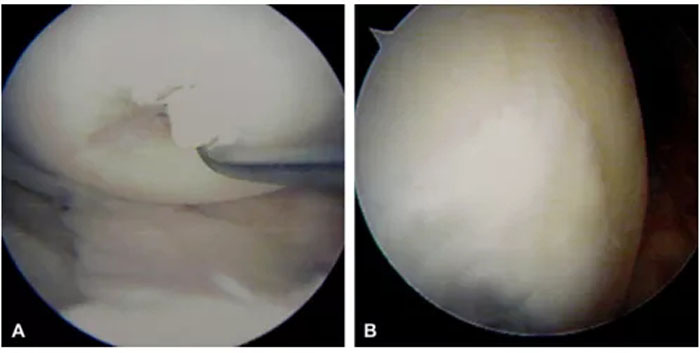

MSCs已被應用于臨床,對于軟骨的修復同樣收到了不錯的療效。一項研究中,受試者是一位31歲的男子柔道運動員,因右膝遭遇傷病而出現間斷性疼痛。股骨內側髁負重區發現20-30毫米全層軟骨缺損。在患者知情同意的情況下,用其自身的MSCs治療軟骨損傷。術前4周,從患者髂骨吸取骨髓,去除紅細胞后,擴增剩余的細胞。收集貼壁細胞并將其植入到膠原凝膠中,然后將膠原凝膠轉移至股骨內側髁軟骨缺損處,其中種植體被自身骨膜瓣覆蓋。結果顯示,在術后7個月,通過關節內窺鏡檢查發現,軟骨缺損部位被光滑組織所覆蓋(圖4)。術后1年,通過磁共振成像發現,受損部位軟骨水腫消失(圖5),臨床癥狀明顯改善,患者恢復了先前的活動水平,并且右膝不再疼痛,也沒有其他并發癥出現[3]。

圖4:關節內窺鏡檢測結果

A:術前,股骨內側髁負重區發現20-30毫米全層軟骨缺損;B:術后7個月,軟骨缺損部位被光滑組織所覆蓋;